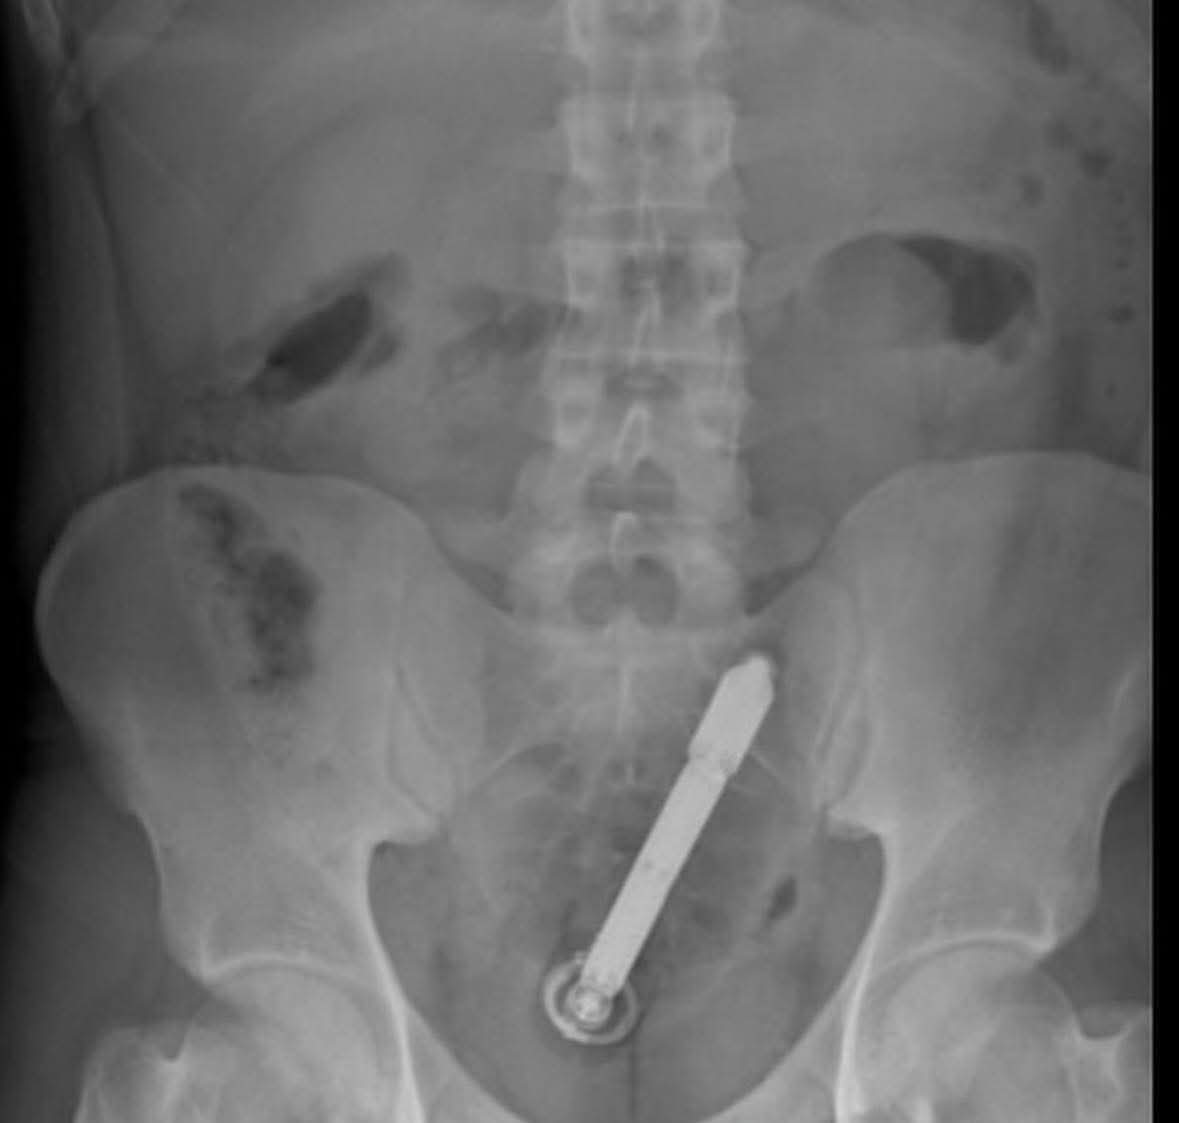

VALVERDE.- Una emergencia inusual se presentó la noche del lunes, en un centro de salud del municipio Mao, en la provincia Valverde, donde un hombre llegó con un palo incrustado en el ano.

Los médicos de turno atendieron al ciudadano identificado con las iniciales R.M.B., trataron de normalizar su estado y lo refirieron a un centro hospitalario en Santiago.